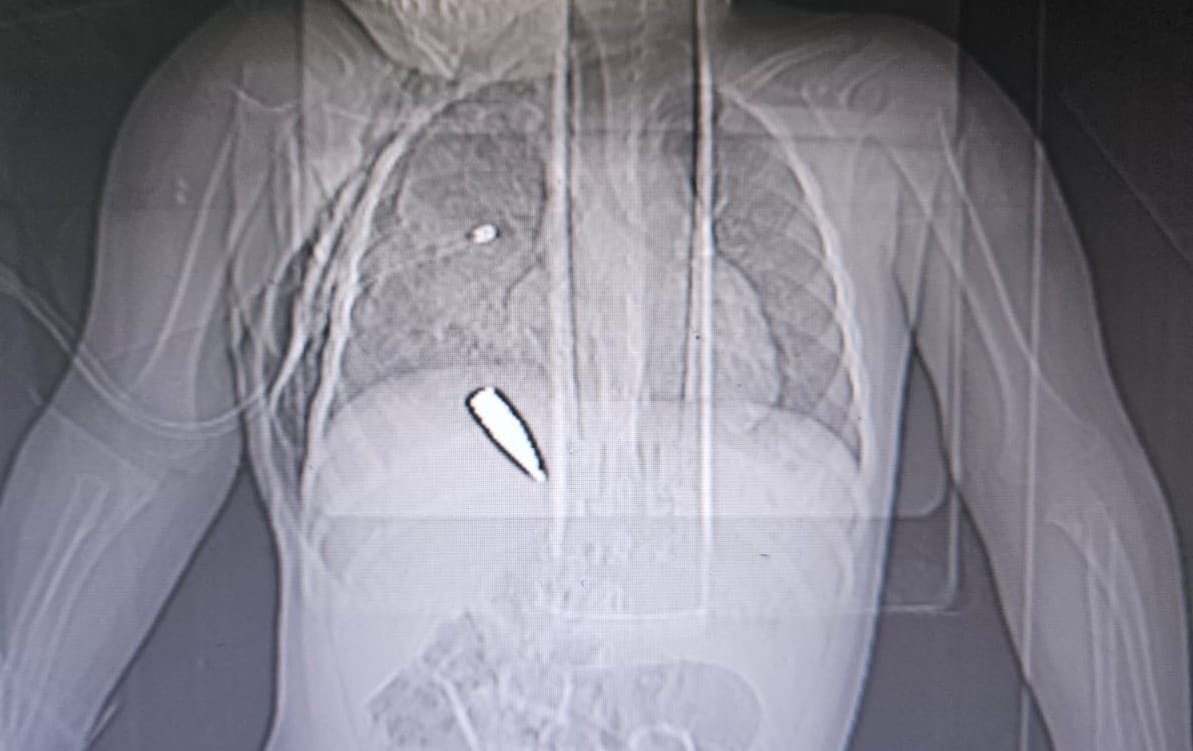

RX di una bambina di un anno e mezzo, colpita da un proiettile mentre era in braccio della madre, in fila a un centro di distribuzione GHF. Foto via X, Gila Project

Medici Senza Frontiere ha pubblicato una nota di condanna contro la distribuzione di aiuti umanitari gestita dalla Gaza Humanitarian Foundation. L’Ong usa termini durissimi per lo schema di distribuzione della GHF, dopo l’inchiesta di Haaretz che ha rivelato come i militari israeliani abbiano ricevuto ordini espliciti di sparare sugli affamati che si avvicinano ai centri di distribuzione. “Con più di 500 persone uccise e quasi 4.000 ferite mentre cercavano cibo, questo schema è un massacro mascherato da aiuti umanitari,” scrive MSF, “e deve essere immediatamente smantellato.” L’organizzazione “chiede alle autorità israeliane e ai loro alleati di cancellare l'assedio che impedisce l’ingresso alle forniture alimentari, mediche e umanitarie, oltre che al carburante, e di tornare al sistema precedente, coordinato dalle Nazioni Unite, basato su principi umanitari.” Non si tratta di un incidente, secondo l’Ong: “Questo disastro è stato orchestrato dal proxy israeliano–statunitense che opera sotto il nome della Gaza Humanitarian Foundation.” Aitor Zabalgogeazkoa, coordinatore di MSF a Gaza, spiega in modo secco: “Se le persone arrivano in anticipo e si avvicinano ai checkpoint, gli sparano. Se arrivano in orario, ma ci sono troppe persone… gli sparano. Se arrivano tardi, non dovrebbero essere lì perché si tratta di una ‘zona evacuata,’ e gli sparano.” I centri di distribuzione dovrebbero essere aperti solo un’ora al giorno — ma spesso sono aperti anche solo pochi minuti, e l’apertura e la chiusura dei centri è annunciata solo mezzo social media, con preavvisi di pochi minuti. MSF conclude: “Gli aiuti non devono essere controllati da una parte attiva nel conflitto per favorire i propri obiettivi militari. Le autorità israeliane hanno usato la privazione del cibo come un’esplicita tattica contro i palestinesi di Gaza.” (Medici Senza Frontiere)